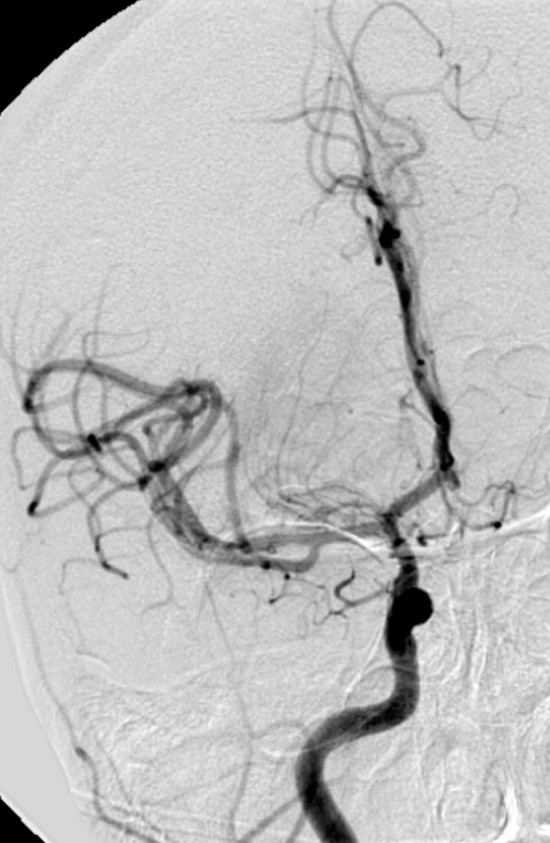

En kvinne tidlig i 30-årene ble innlagt i sykehus med akutte pareser i venstre kroppshalvdel. CT-angiografi viste okklusjon av høyre a. cerebri medias hovedstamme, og det ble startet intravenøs trombolytisk behandling. Under pågående infusjon ble hun sendt til Oslo universitetssykehus for endovaskulær behandling. Det ble utført vellykket embolektomi, med rekanalisering av arterien og rask klinisk bedring. Angiogrammene viser venstre fremre kretsløp før (venstre) og etter (høyre) prosedyren. National Institutes of Health Stroke Scale (NIHSS) ble skåret til 11 poeng ved innkomst (moderat alvorlig hjerneslag), 4 etter prosedyren (milde slagsymptomer) og 1 ved utskrivning (nær symptomfri). Av kjente vaskulære risikofaktorer bemerket vi røyking og bruk av p-piller.